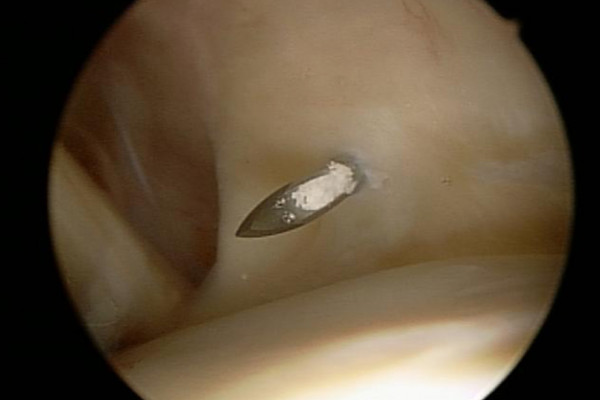

Der in der Sehne gelegene Kalkherd wird mit einer Hohlnadel (Bild 2) (der Kalk bleibt in der Nadelöffnung hängen) lokalisiert, danach wird der Kalk nach Eröffnung der betroffenen Sehne mit einem Löffel (Bild 3) möglichst vollständig entfernt und abgesaugt.